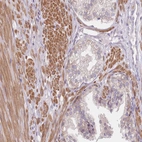

Immunohistochemical staining of human endometrium shows moderate cytoplasm granular positivity in glandular cells.